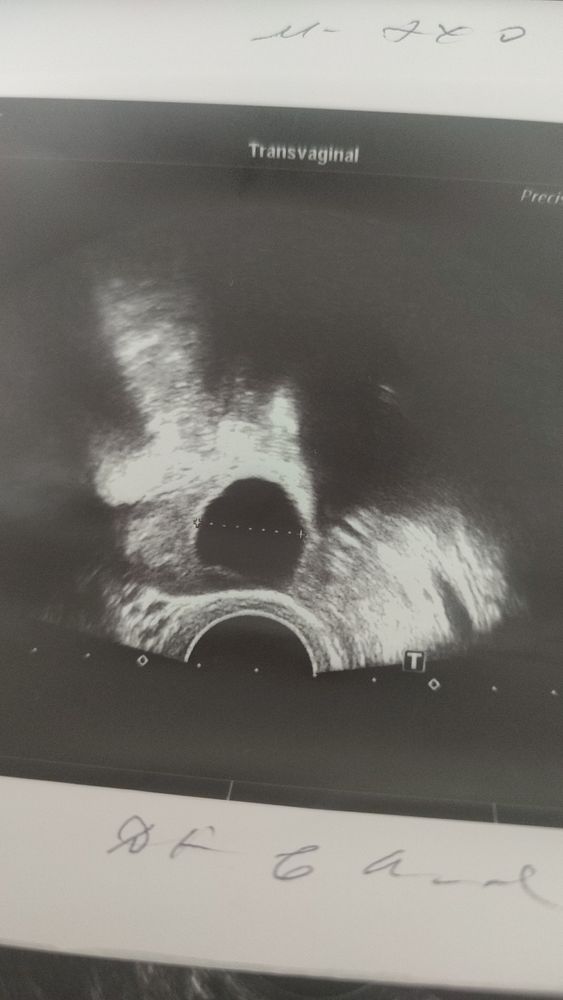

19 мм хороший фолликул. Может совулировал, либо это еще впереди. Уже 23 дц, а цикл у вас длинный вообще? Похоже на позднюю овуляцию. Но жидкость может по разным причинам быть, не только от овуляции. Тут непонятно. Переделайте узи через пару дней.

Могло просто еще не сформироваться, часто такое бывает, что видят жидкость, а ЖТ нет. ЖТ формируется по разному, у кого-то сутки, а у кого-то на 3-4 день после овуляции только его видно.

Скорее всего в момент овуляции были. Фолликул только надорвался, фолликулярная жидкость вышла, а желтое тело еще не сформировалось. Повторите УЗИ через 2 дея